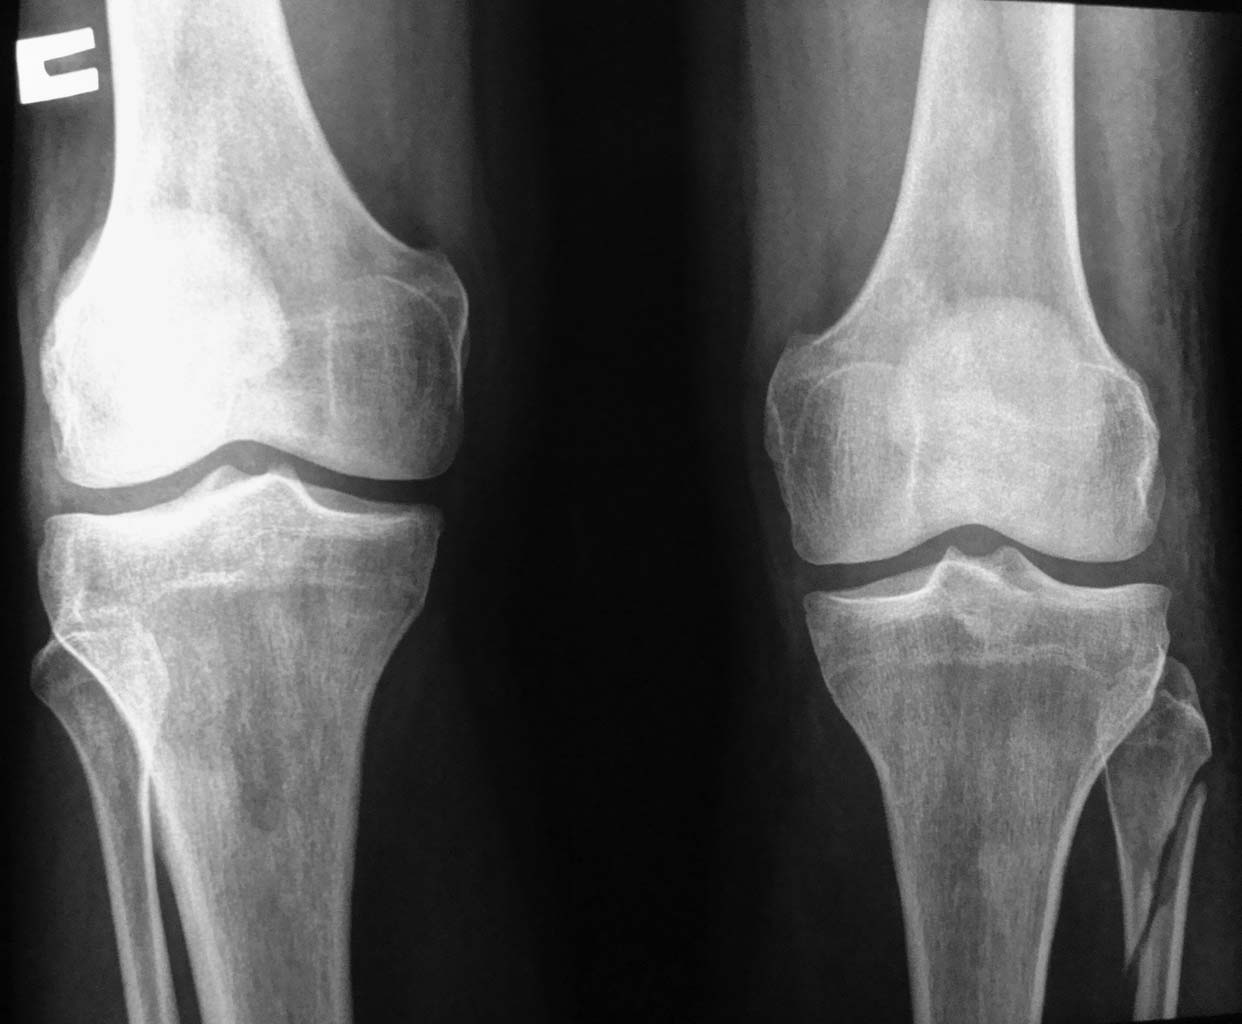

Уважаемые коллеги!  Нужна ваша помощь. В нашу больницу из районной ЦРБ 14.09.12г

переведен пациент 29 лет, травма незначительная - шел в баню и подвернул левую ногу. Ранее

никогда ничего не беспокоило, вел обычный образ жизни, не курит, наследственный анамнез не

отягощен. Никогда ничем не болел, кроме ОРВИ редко. Локально - голень без изменений, кожа

спокойная, стопа и голень теплая, чувствительных и двигательных расстройств нет.

Выполнены Rg-черепа, грудной клетки,таза и правой голени-патологии не выявлено. С

коллегми проводим диф.диагностику между остеобластокластомой, адамантиномой и

эозинофильной гранулемой. У кого какое мнение и тактика в данном случае. Заранее всем

спасибо за участие и советы.